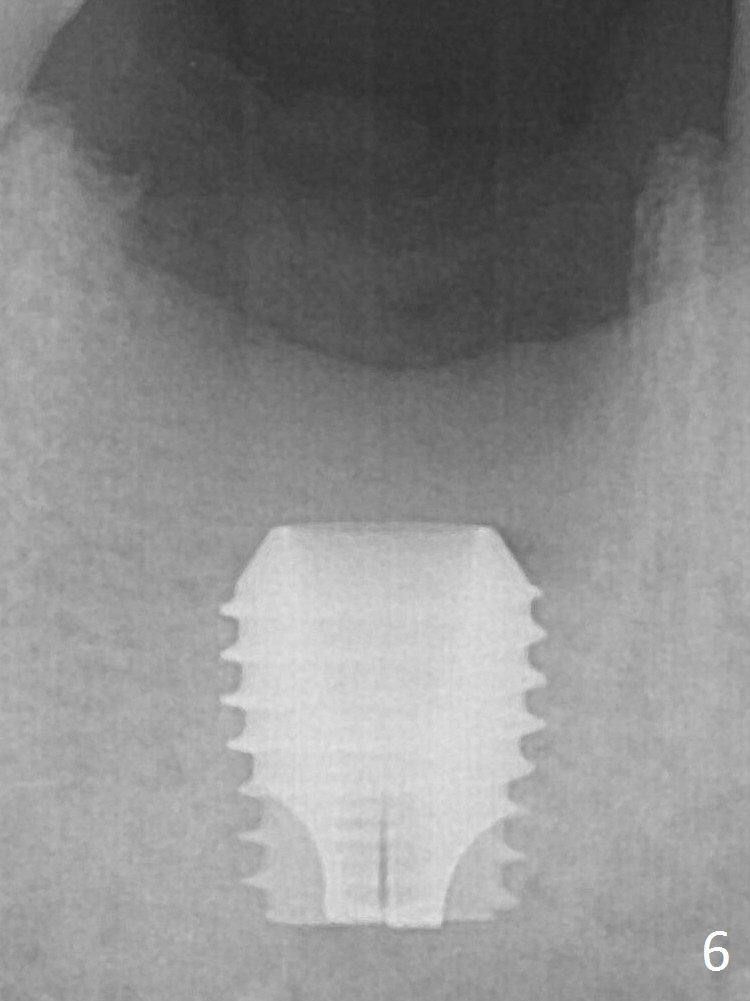

A 5.9x6 mm SM implant is placed with >50 Ncm following Septocaine infiltration (Fig.6).